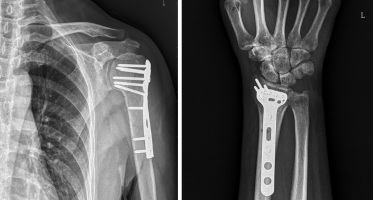

图2. 左侧肱骨近端、桡骨远端骨折内固定术后改变

阅片后与王女士沟通,骨折愈合良好,但由于术后关节固定时间较长,导致关节粘连、肌力下降的情况,进而引起肢体运动障碍,急需要系统康复治疗的介入,自我康复可能达不到理想的效果,王女士表示会积极配合相关康复治疗。除了一般关节松动治疗、肌力激活增强训练等,治疗师还为其开展手法消肿、瘢痕松解等训练内容,以改善术区血液训练、淋巴液回流功能;此外训练前后还配合物理因子治疗,并指导王女士进行家庭康复。循序渐进,每周复诊都会发现王女士的进步,进行为期一个多月的康复训练后,王女士术区胀痛基本改善,皮肤弹性明显增加,现在也能够自如地进行洗脸、梳头、握拳了,王女士很是欣慰,最后一次门诊复诊,她感叹道:如果术后能早点来做康复就好了,以前认为康复没啥用,亲身体验后才发现早康复早获益啊。